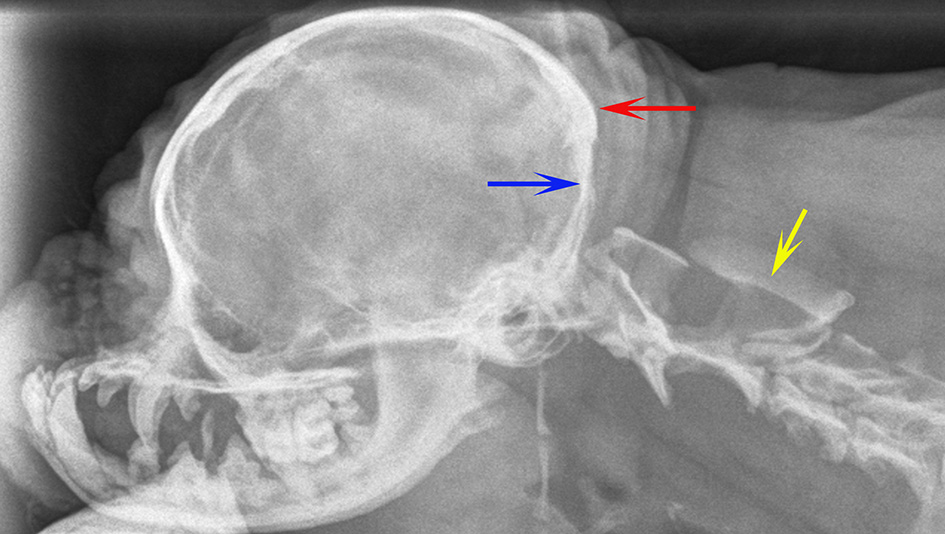

Figure 1

Lateral skull and cranial cervical spinal radiographs in a Griffon Bruxellois with MRI confirmed severe CM and SM (A), a normal Griffon Bruxellois (B), and an Australian terrier (C). The head is in extension as the space between the dorsal atlas and the occiput increases with flexion. A red arrow is placed between the occiput and the dorsal tubercle of the atlas for each dog. The atlas is considerably closer to the skull in the SM affected dog.

Lateral skull and cranial cervical spinal radiographs of a 6 year old female Griffon Bruxellois presented with tetraparesis and following MRI diagnosed with symptomatic CM and SM. The skull has rostro-cranial doming and a “copper beaten” appearance due to convolutional markings relating to the gyri and presumed raised intracranial pressure. The supraoccipital bone is flattened (blue arrow) and the occipital crest is small (red arrow). A large cervical syrinx has resulting in widening of the cervical spinal canal with thinning and scalloping of the vertebrae (yellow arrow). A MRI confirmed CM, SM, and ventriculomegaly. The maximum width of the syrinx in the cervical spinal cord in a transverse section at the level of C2 was 8 mm.